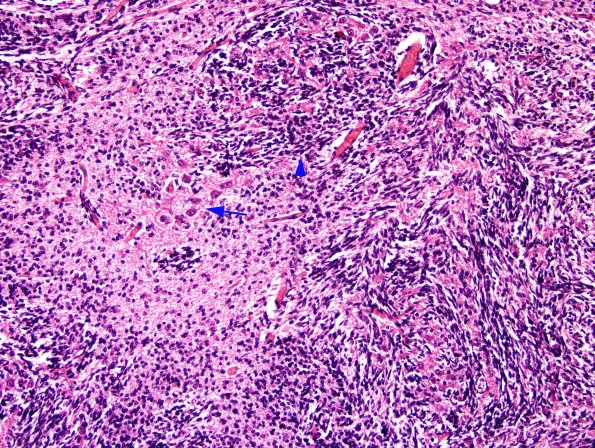

In addition to heterotopia in the frontal lobe, the cerebellum shows collections of poorly organized dysplastic mixed cell rests containing mature neurons (arrow) and immature neuroepithelial cells (arrowhead, which has also been called "heterotaxia" of Brun). (H&E)